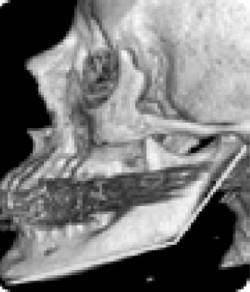

Иллюстрация к книге — Биогимнастика для лица: система фейсмионика [i_018.jpg]

Рис. 13а. Спрямление шейного отдела

Иллюстрация к книге — Биогимнастика для лица: система фейсмионика [i_019.jpg]

Рис. 13б. Гиперлордоз шейного отдела